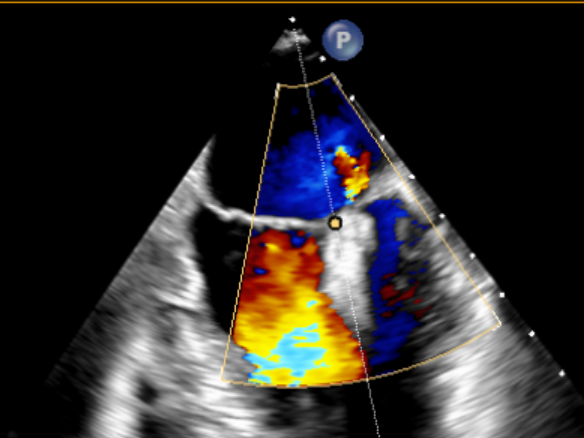

患者全麻后在超声和射线引导下穿刺股静脉-房间隔,器械顺利到达病变的二尖瓣区域,成功完成二尖瓣夹合后,患者二尖瓣反流即刻显著下降,左房压力即刻减低,预示着患者的临床症状将会得到明显改善。